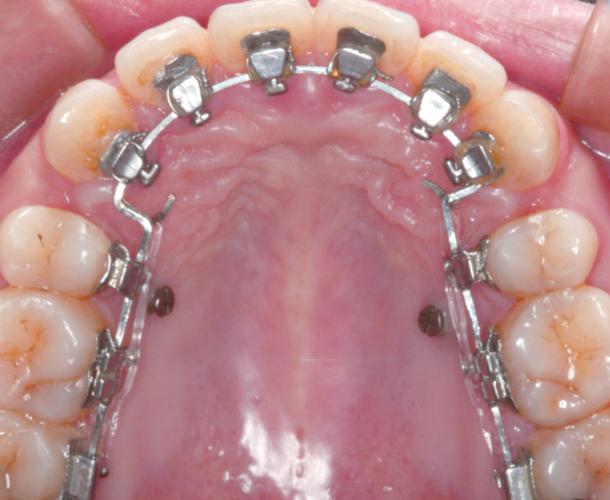

粘接时,医生先用酸蚀剂处理牙齿表面(通常为30%-40%磷酸酸蚀30秒),以形成微小孔隙,增强粘接剂与牙齿的机械嵌合力;冲洗吹干后,涂布底剂(如含硅烷偶联剂的树脂底剂),提高粘接剂与牙面的化学结合力;随后将专用粘接剂(多为光固化树脂)涂于托槽底板,精准放置于牙齿预定位置,用探针调整位置后,用光固化灯照射20-40秒使树脂完全固化,最后去除多余粘接剂,检查托槽边缘是否密合、有无悬突,整个过程需在干燥环境下操作,避免唾液或血液污染,否则易导致托槽脱落。